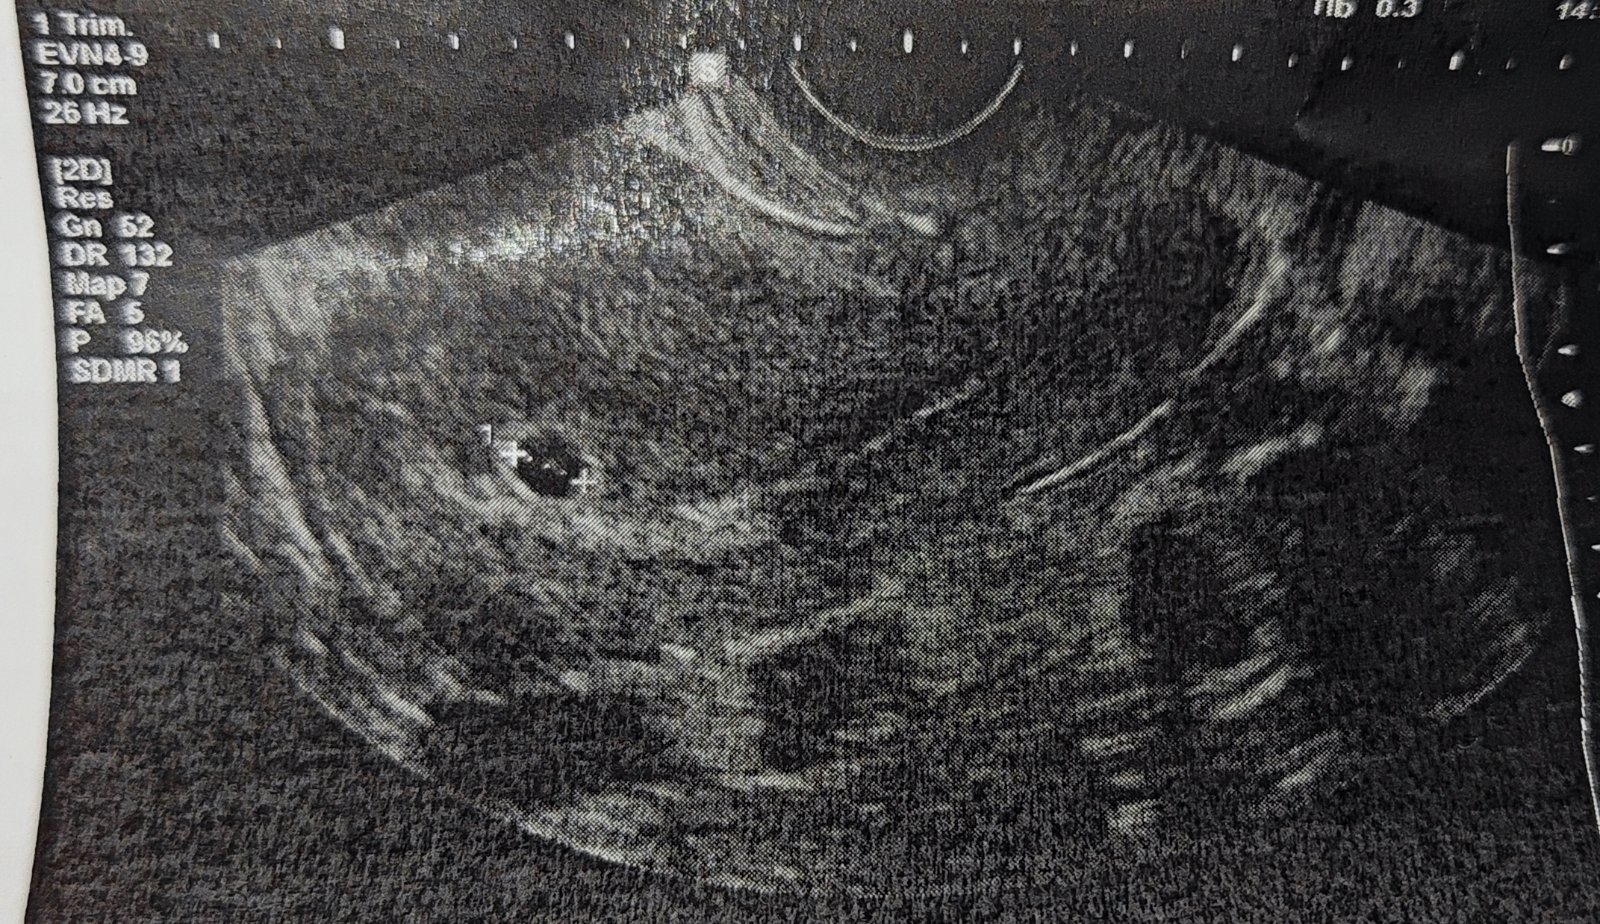

Je na ultrazvuku viditeľný žĺtkový vak?

Ahojte ... Bola som na sone v 6+0tt a dr videla gestačny vak 7-8mm a že je to taky 4+6tt ... Ja som po inseminácii tak neviem či je tam možnosť takého rozdielu ... Veľmi sa bojím keďže pred vyše rokom sme prišli o bábätko v 20tt ... Mám aj fotku zo sona myslíte že tam je aspoň ten zltkový vak ? Mne sa tam niečo zdá keď si fotku priblížim ako keby tam boli bublinky ale neviem ako presne má vyzerať ten zltkový vak ...

@henrietka12 keby doktorka videla zltkovy vak, povedala by. . Ak je vidiet zltkovy vak, mali by byt vidiet aj embryonalne struktury. Musis pockat do dalsej kontroly, nic ine... drzim palce